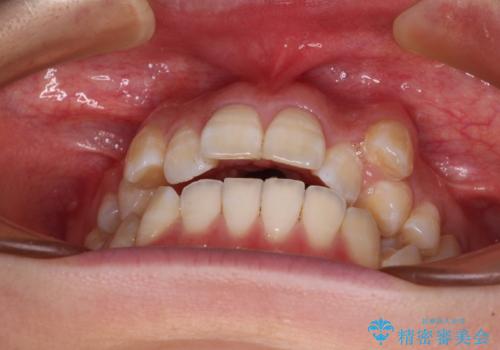

八重歯と開咬の抜歯矯正 ワイヤー装置を併用したインビザライン矯正治療

- 咬み合わない前歯と八重歯などのデコボコを気にして来院された患者様です。

上下前歯の位置を比較すると上顎が前方にあり、デコボコ改善でより上顎が前方に行く可能性があります。

インビザライン矯正治療では、臼歯の圧下による前歯部の早期接触が大きな問題となっています。開咬では、その臼歯圧下を逆手にとって前歯部の非接触を改善させることができます。